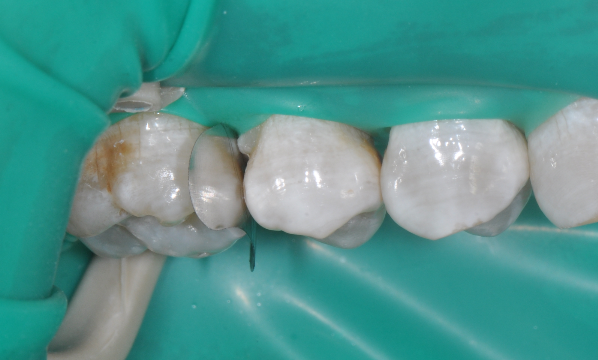

牙医-马小寒【实操病例】

右上6号牙位的近中,可见隐约龋坏

◆去腐完成之后

◆该成形片能更好的将龈缘区域的边缘封闭性做的更好。尤其是在邻面区域,涂布第六代粘结剂,固化粘结剂之后,配合高填料流体树脂和后牙专用树脂进行该洞形的充填。

◆术后即刻照,如果邻面边缘出现悬突,可以使用12#手术刀去除,再配合抛光条抛光

◆术后撤离橡皮障后口内照片,术后1周复查,我们修正了边缘嵴的斜度及邻面轴线上的多余材料;复查是很重要的,能够发现第一次操作的时候遗留的不足,并且再次修正,保障了充填体的寿命。该案例也得益于改善了的成形片,修正了以往的成形片邻面龈缘区域材料残留形成过多的悬突材料,避免了术后龈乳头炎的发生!